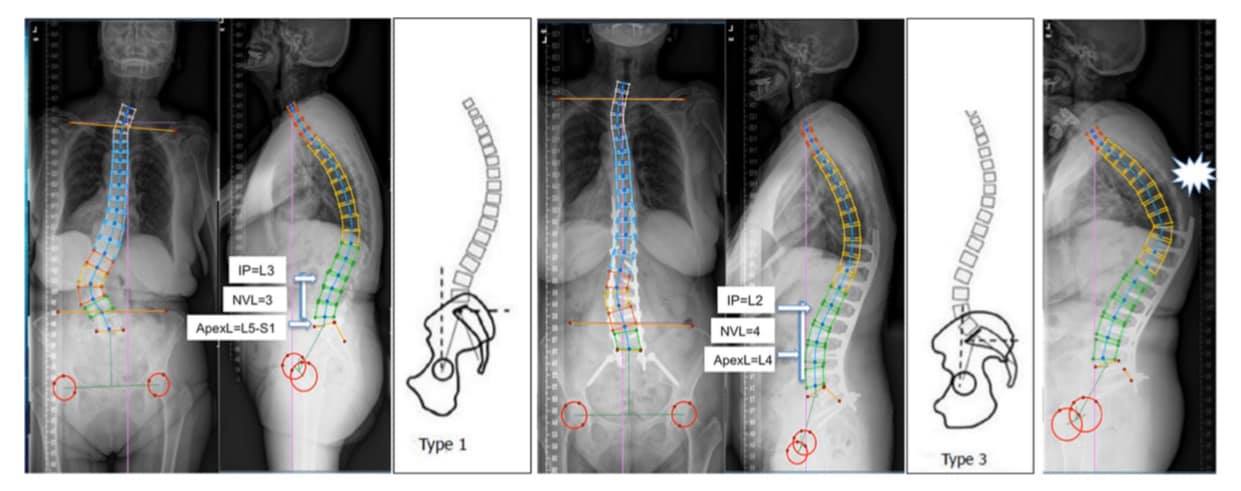

Restaurar el perfil sagital Roussouly ideal en la cirugía de escoliosis en adultos disminuye el riesgo de complicaciones mecánicas.

• Todavía no hay datos que demuestren si la restauración del perfil sagital ideal (según la clasificación de Roussouly) en pacientes adultos con escoliosis (AS) conlleva algún beneficio adicional, especialmente con respecto a complicaciones mecánicas.

• La cirugía de escoliosis en adultos debe restaurar el perfil sagital Roussouly ideal para disminuir la tasa de complicaciones mecánicas, especialmente en pacientes mayores de 65 años, instrumentados en la pelvis.

Restoring the ideal Roussouly sagittal profile in adult scoliosis surgery decreases the risk of mechanical complications.

Adult deformity surgery; Adult scoliosis; Mechanical complications; Roussouly classification; Sagittal profiles